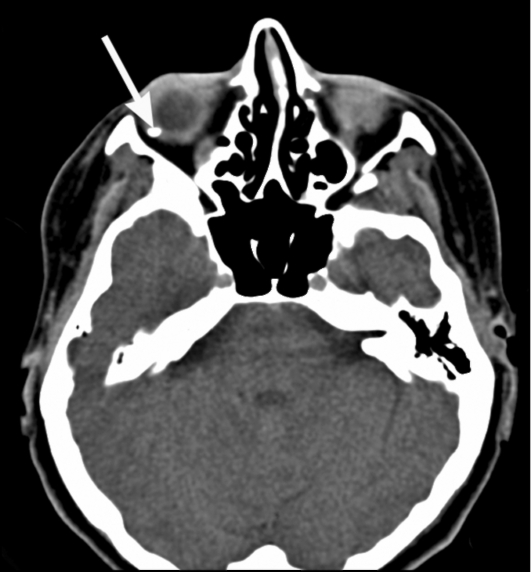

КТ: метод выбора для выявления

рентгеноконтрастных инородных тел (рис. 7).

Рис. 7. Компьютерные томограммы. Инородное тело

правого глазного яблока (стрелка)